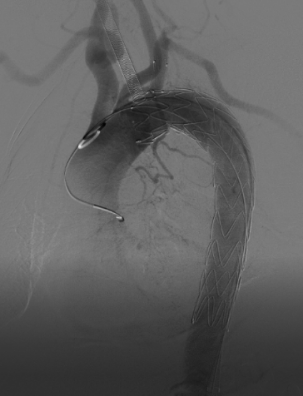

*术后造影:溃疡立刻消失,手术效果立竿见影